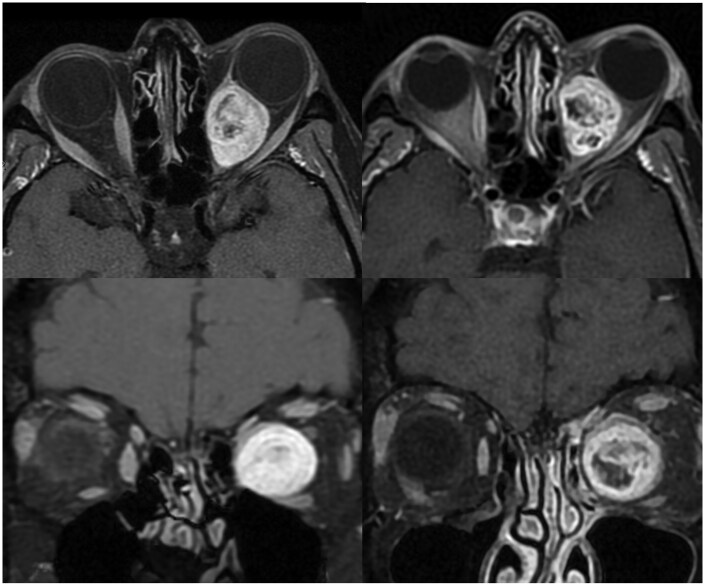

Results: Eight patients were included in our study, six patients with an optic nerve sheath meningioma, one cavernous haemangioma and one orbital schwannoma. All patients demonstrated tumour regression, mean tumour volume prior to treatment of was 4916 mm3 and reduced to 3239 mm3 (P = .03). Three of eight patients showed improvement of visual acuity, three retained excellent pre-treatment vision and two patients had a reduction of vision. HA and VMAT planning target volume coverage dosimetry was similar (D95%: 98.7% and 98.6%, P > .05). The dosimetry of the contralateral lens (32.2 vs 69.8 Gy), lacrimal gland (1.7 vs 7.8 Gy), optic nerve (9.0 vs 26.6 Gy), nasal cavity (10.2 vs 20.6 Gy) and ipsilateral temporal lobe (4.9 vs 11.6 Gy) was significantly improved (P < .001) with HA.

Conclusion: This is the first reported clinical application of HA for benign orbital tumours. HA was an effective and well tolerated treatment modality. HA offered better dosimetry for some of the OARs compared to VMAT.